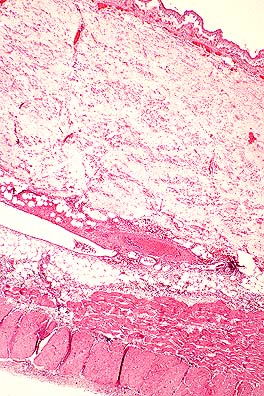

Marked hepatic portal fibrosis in a mouse injected with S. mansoni cercaria 3.5 months previously. (HE, 20X, 58K)

Gross Pathology: The liver was yellow-brown to tan and had a granular appearance.

Contributor's Diagnosis and Comments: Liver: hepatitis, chronic, portal and bridging, multifocal, moderate, with granuloma formation, trematode eggs, pigment, and intravascular trematode parasites - etiology consistent with Schistosoma mansoni.

AFIP Diagnosis: Liver: Hepatitis, portal and bridging, chronic, multifocal, moderate, with granulomas, trematode eggs, and intravascular trematodes, Swiss-Webster mouse, rodent, etiology consistent with Schistosoma mansoni.